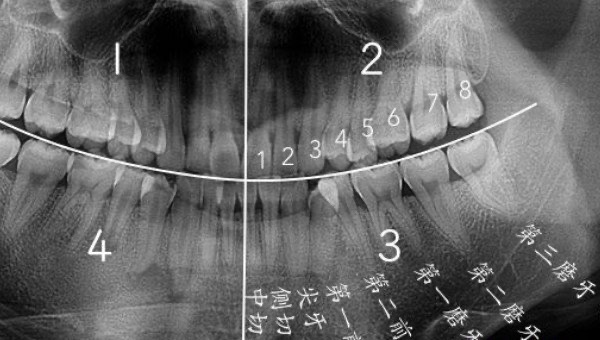

智齿是人类口腔内牙槽骨上最里面的第三颗磨牙,由于它经常会产生疼痛感,很多人选择将其拔掉,但部分人表示拔智齿后悔死了,那么这是为什么呢?快和小编去看看吧。

人在成年之后一般都会长智齿,在其生长期间可能会出现牙龈肿痛的情况,严重影响人们的日常生活,所以很多医生都建议将其拔掉,但总有人会因为拔掉后出现的不良反应而后悔。【周边网】事实上,智齿对人的危害没有那么大,如果其生长状态比较良好,则没有强行拔除的必要,除非是畸形智齿。